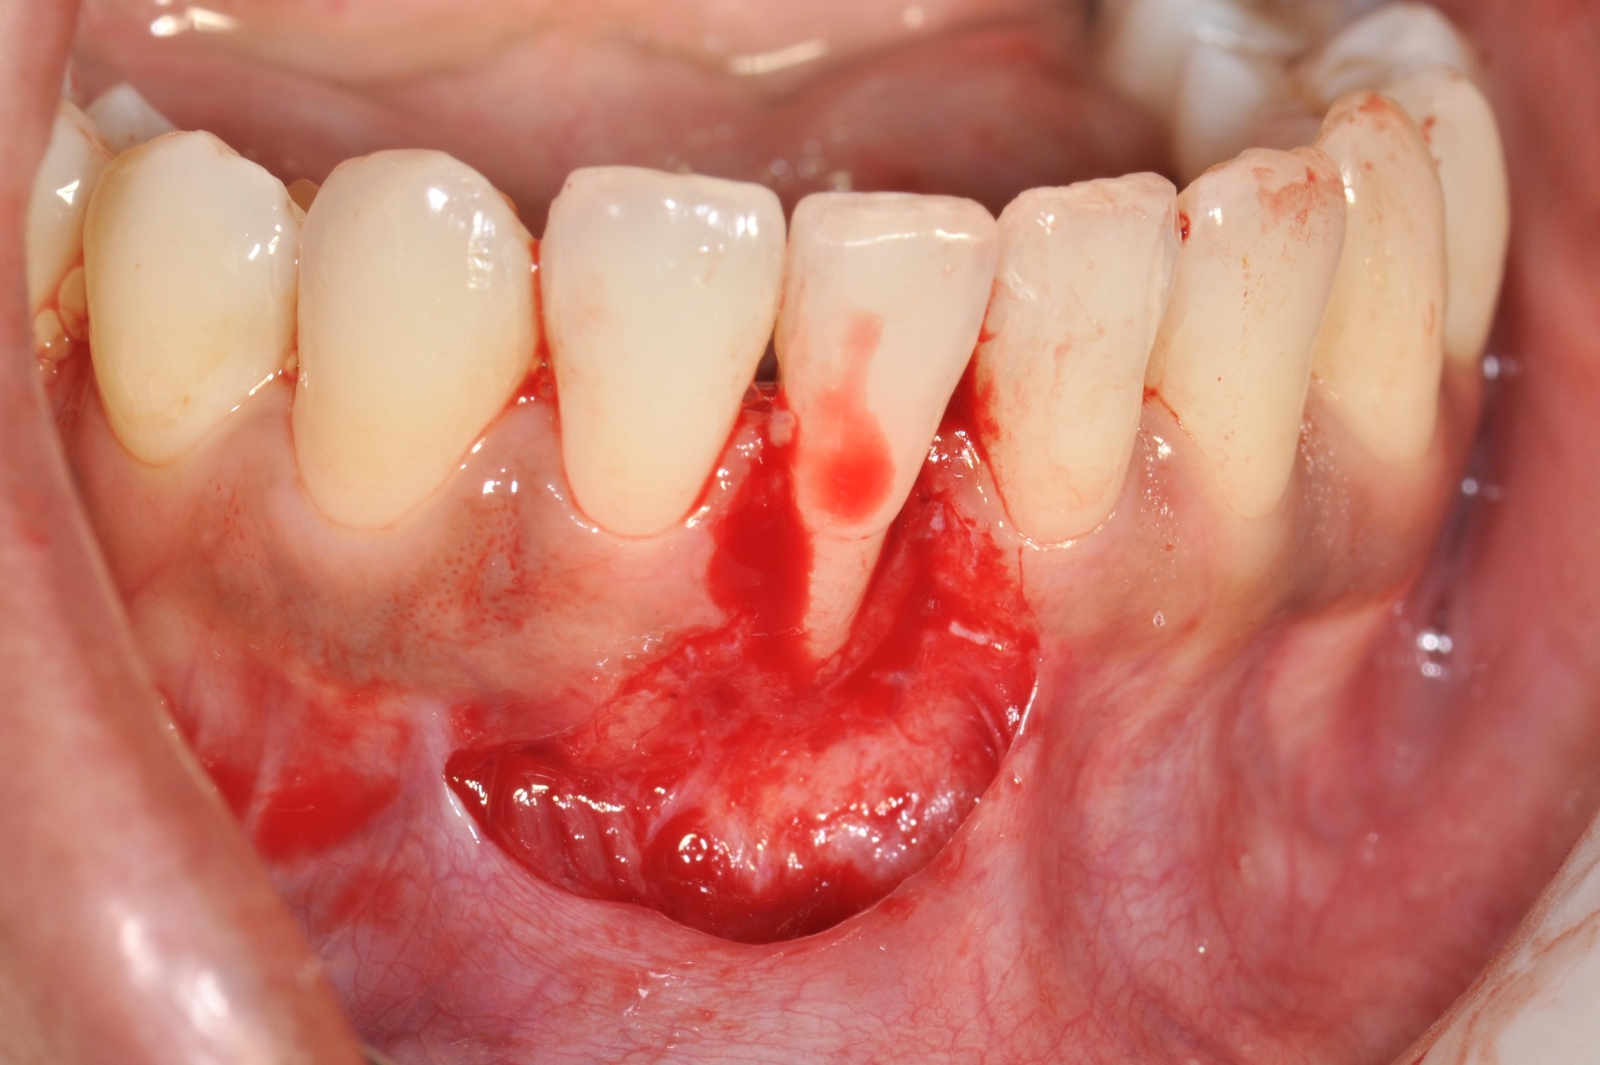

Celles-ci incluent la chirurgie à lambeaux pour un nettoyage en profondeur, la greffe gingivale ou conjonctive afin de renforcer les tissus, et la chirurgie du sourire gingival (ou "Gummy Smile") pour réharmoniser l’esthétique du sourire.

- Chirurgie à lambeaux

- Greffe Gingivales et conjonctives